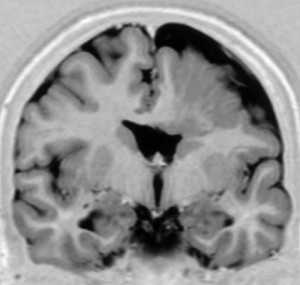

МРТ. Т1-зависимая корональная томограмма. Агирия.

Лиссэнцефалия - это общий термин, под которым понимают нарушение формирования борозд. Крайнее проявление ее - полное отсутствие извилин - агирия. Серое вещество имеется, но оно не разделено бороздами. Агирия может быть локальной, обычно этот тип наблюдается в височной доле.

Аномально малое число извилин в связи с неполными бороздами называется пахигирией. Обычно, она также локальная, извилины широкие и сглаженные. Сочетание участков пахигирии и агирии называют лиссэнцефалией I типа. При МРТ определяется утолщение коры, вертикальные Сильвиевы борозды и часто выпрямленные гиппокампы. Клинические проявления укладываются в различные формы (синдромы Миллера - Декера, Нормана - Робертса и т.д.), проявляющиеся в первый год жизни. Тип II отличается нарушением структуры самой коры, которая пронизана сосудами и фиброглиальными пучками. Этот тип сочетается с гидроцефалией и неполной миелинизацией. Характерно клиническое проявление в виде синдрома Уокера - Варбурга.